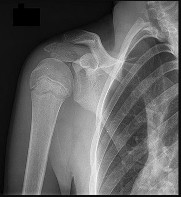

A 9-year-old boy has a history of multiple fractures. He presents with left leg pain following a minor fall. His anteroposterior

() and lateral () plain radiographs are shown. The most likely genetiCdefect would be:

In osteogenesis imperfecta, the genetiCdefect involves type I collagen. Type I collagen is made up of two alpha-1 chains and one alpha-2 chain in a triple helix. Glycine is the smallest amino acid and is crucial for coiling of the triple helix. Mutations in the

glycine chain lead to severe forms of osteogenesis imperfecta. One should also remember the Silence classification:

Type Inheritance Sclera Severity

I AD Blue Mild form, normal teeth

II AR Blue Lethal form, die early

III AR Normal Severe, progressively deforming

IV AD Normal Moderately severe

Biphosphonate therapy can be used to slow bone remodeling and increase bone mass. With regard to the incorrect choices:

FGF receptor 3 is associated with achondroplasia. Fibrillin is associated with Marfan's syndrome.

Type II collagen is associated with spondyloepiphyseal dsyplasia.

Cartilage oligomeriCmatrix protein is associated with pseudoachondroplasia. Correct Answer: Type I collagen